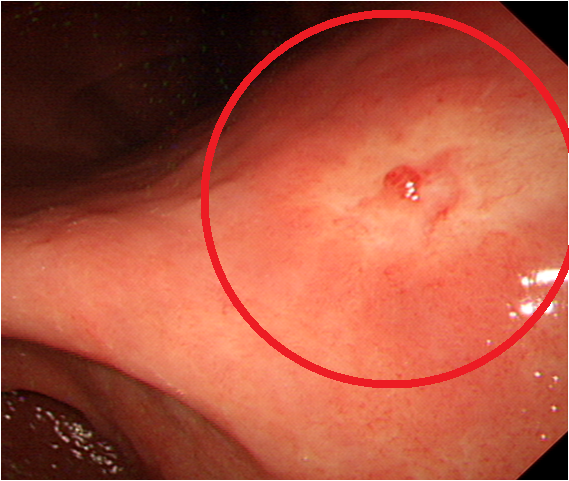

위암 환자들은 소화관에서 출혈이 발생할 경우, 흑색 변이나 혈변이 나타날 수 있습니다. 이런 증상은 위장 내 출혈의 신호로, 특히 주의해야 합니다. 일반적으로 성인의 경우, 변의 색이 갈색이 아닌 검은 색으로 변한다면 즉시 의사의 진찰을 받아보아야 합니다.

혈변 또한 심각한 문제의 신호로, 보통 위장관의 상부에서 출혈이 나타날 가능성이 높습니다. 이 문제는 메스꺼움이나 복부 통증과 동반될 수 있으며, 조기 검진이 필수적입니다. 건강을 유지하기 위해 이상 증상이 의심될 경우 빠르게 전문가의 도움을 받는 것이 중요합니다.